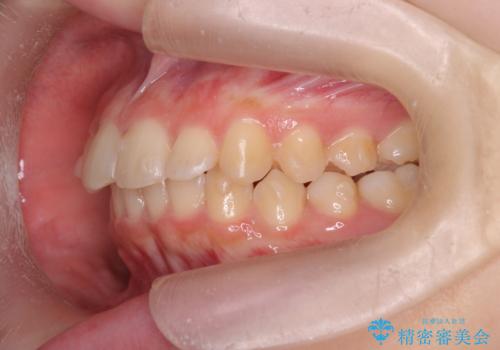

- 突出感のある、前歯の矯正治療を求めて来院されました。

軽度な突出・ガタつきを26枚・約半年の矯正治療期間で計画するインビザラインモデレートプランで治療を始めて行きます。

約半年といった短期間で、前歯の角度やガタつきを改善することができました。